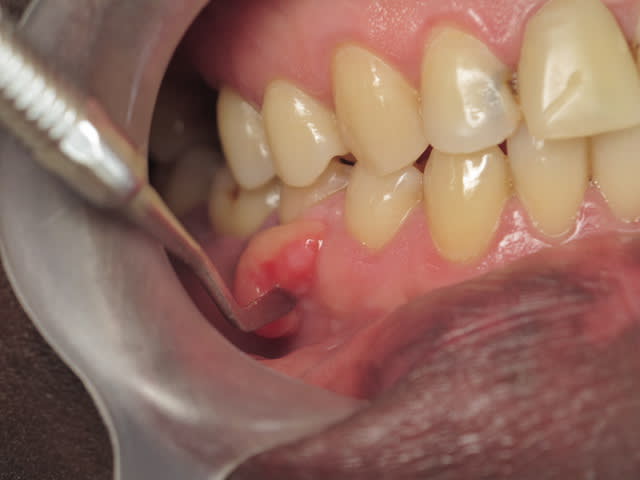

La panoramique montre une image radioclaire suspecte au niveau de la branche horizontale mandibulaire, entre 44 et 45 justement. Le patient n'en avait pas connaissance.

sinon l'image radioopaque (et non radioclaire comme mentionné) n'a rien de particulier, ne pas s'en soucier.

Ok, donc l'image radio-opaque (pardon pour la confusion) au niveau de la branche horizontale ne serait qu'une coïencidence ? Mais alors qu'est ce que c'est ?

=> Oui probable coincidence. Il faudrait pouvoir consulter d'anciens clichés (genre y'a 10 ans) pour comparer les images et suivre cette évolution.

=> sinon c'est une probable ostéosclérose focale idiopathique (sans cause évidente.